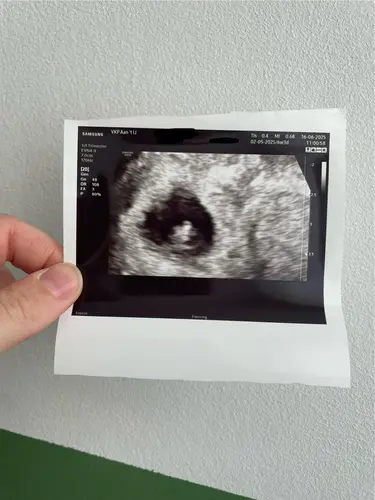

Vandaag mijn eerste (vroege) echo gehad. Ben paar dagen teruggezet 5+6 ipv 6+2 zoals ik zelf dacht. Alles zag er mooi uit en ook het hartje zien kloppen. 1,7 mm is onze inimini.